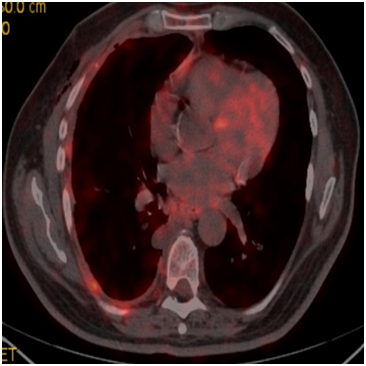

A sixty-five year-old male patient was admitted to our clinic with complaints of cough and shortness of breath for 7-8months. He was an active smoker for forty-five packets/year, he had not asbestos exposure. 1000cc serohemorrhagic fluid was drained from the patient. No malignant cells were detected on cytological examination. Parasternal emphysema in both lungs, volume loss in right hemithorax and advanced pleural effusion were observed in thorax computerized tomography (CT). Fluorodeoxyglucose (FDG) uptake (SUV max, 7), FDG uptake in several lymph nodes (SUV max, 3.7-4.8) in the right sub paratracheal and subcarinal area of the mediastinum (Figure 1) were present in plaque-like pleural thickening areas be about more pronounced in the middle and lower zones in positron emission tomography (PET-CT) on almost all surfaces of the right hemithorax pleura. Video-assisted thoracic surgery (VATS) was performed with mesothelioma doubt. Tumor showing vascular invasion in places was observed in the form of multifocal small foci and nodulations on visceral and parietal pleura in pathological examination of wedge resection and partial parietal pleuractomy material taken from right lung upper lobe and lower lobe. In immunohincistochemical researches, TTF-1 (thyroid transcription factor-1), CEA (carcinoembryogenic antigen) and CK-7 (cytokeratin-7) were positive,staining with CK20, CK5/6, Melone A, HMB45, WT1 (Wilms tumor) and calretinin was not seen (Figure 2A) (Figure 2B). Intraplasmic mucin staining was detected with PAS-Alcian Blue histochemical staintumor primer was evaluated as lung adenocarcinoma. Progression and pulmonary embolism developed after the 3rd cure in patient who underwent chemotherapy after pleurodesis. The patient died with respiratory insufficiency at the fifth month of follow-up.

Figure 1 FDG (SUV max:7) uptakes in plaque-like common pleural thickening areas be about more pronounced in the middle and lower zones on almost all surfaces of the right hemithorax pleura.